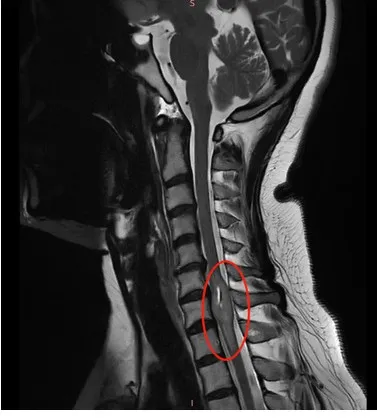

当检查发现“颈7水平脊髓占位病变”,就是在是颈椎的第七节里面长了一个肿瘤时。我首先想到的是,这个要手术吗?

检查结果出来后,医生告诉我颈椎部位长了个肿瘤。

几乎一夜没有睡,查阅资料到第二天早晨,我已经完全弄清楚了病情的严重性和可能带来的影响……脊髓是大脑与身体之间信号传递的“主干道”,周围密布神经纤维,一旦受损,严重可瘫痪。